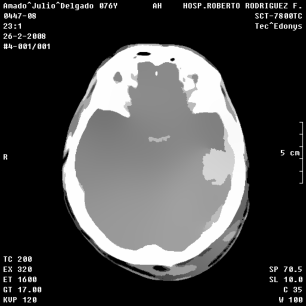

An example of an applications of our proposed strategy to a medical image is shown in Figure 7. In this case, we used different values of and in the . This is a preliminary result. A deeper paper about these results will be published.